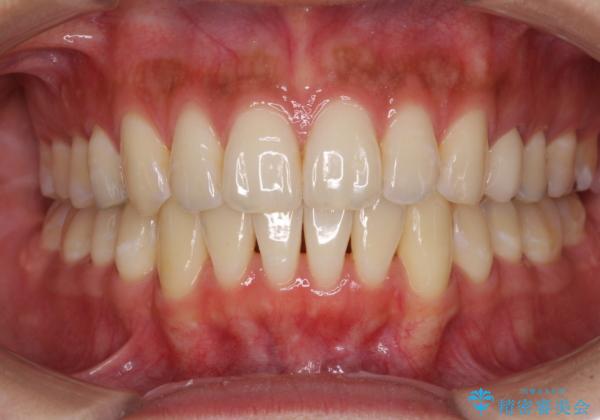

八重歯の再矯正 インビザラインでストレスなく矯正治療

下顎の八重歯が上顎歯列に収まる過程で咬みにくさがありましたが、最終的には、咬み合わせも安定し、きれいに歯列を整えることができました。